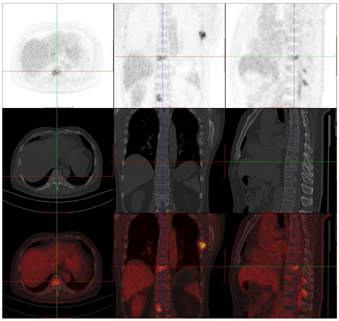

头颅顶可见术后瘢痕,愈合可,后颈可见一长约10 cm术后愈合瘢痕。头颅压痛、包块。发病来,患者神志清,精神可,睡眠可,饮食及大小便正常,体重无明显变化。2021年10月8日行PET-CT示左侧额顶部颅骨术后改变;左侧颞极片状高密度影并邻近骨质破坏,代谢增高(图A);左前纵膈肿块,代谢增高(图B);双肺散在结节,代谢轻度增高(图C);右侧锁骨、左侧第6肋,胸9-腰1、3椎体及其附件骨、双侧髂骨及双侧股骨近端多发混合型骨质破坏,代谢不同程度增高,考虑多发转移瘤(图D,图E,图F);2021年10月10日复查CT示右肺下叶可见结节影,直径约1.5 cm,增强扫描轻度强化;前上纵膈可见类圆形软组织密度影,边界清楚,大小约4.4 cm×3.3 cm,增强扫描轻度强化。于2021年10月11日在局部浸润麻醉下行CT引导下经皮纵膈占位穿刺活检术。病理结果示:肺穿刺组织内见恶性肿瘤,符合转移性间变性脑膜瘤。2021年10月13日MRI示:多发胸椎椎体及附件、所扫及L1椎体异常信号,结合病史,考虑为转移瘤可能。